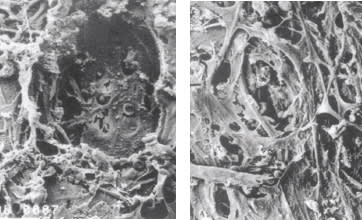

■ Eliminates coagulative damage to the trabecular meshwork and adjacent structures. It does this by confining the laser energy to the target tissue.1 “There’s more physical damage with ALT,” says Catherine Birt, MD, of the University of Toronto. “It is a hot laser. It heats the tissue and coagulates the tissue. Pathology studies show evidence of more structural damage with ALT than SLT in cadaver eyes.” (Figure 1)

Figure 1. ALT histology (left) shows permanent trabecular meshwork damage while SLT histology shows no destruction of the trabecular meshwork.